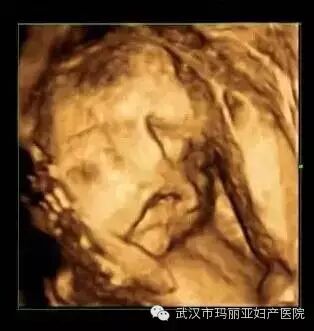

武汉玛丽亚妇产医院引进的世界领先的美国GE-E8四维彩超设备室目前世界上最先进、分辨率最高的彩色超声设备,具有即时立体成像、清晰准确的特点。

它能够多方位、多角度地观察宫内胎儿的生长发育情况,为早期诊断胎儿先天性体表畸形和发育异常提供科学依据。还能对胎儿的体表进行检查,如唇裂、脊柱裂、大脑、肾、 骨骼发育不良等,以便尽早的进行治疗。

玛丽亚美国GE-E8四维彩超排畸成功案例

玛丽亚目前已拥有三台四维彩超机器设备,是武汉乃至湖北拥有较多台四维彩超的妇产专科医院。四维彩超检查的专业性更强,因此它对操作人员的技术与经验要求很高,也只有准确熟练的手法才能达到最佳的检查效果,才能更好的向让准妈妈准爸爸们展示宝宝人之初的惊艳亮相。